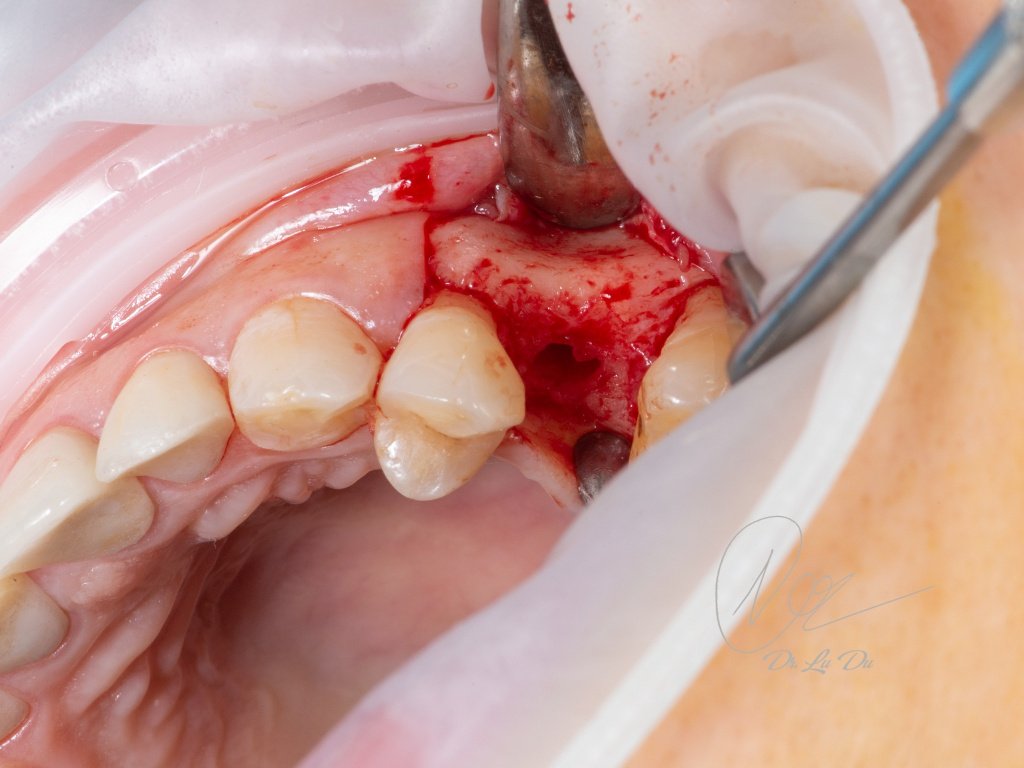

Имплантация AnyRidge с двусторонним закрытым синус-лифтингом.

Осложнения: правосторонний гайморит.

Кейс MINEC: Dr Lu Du